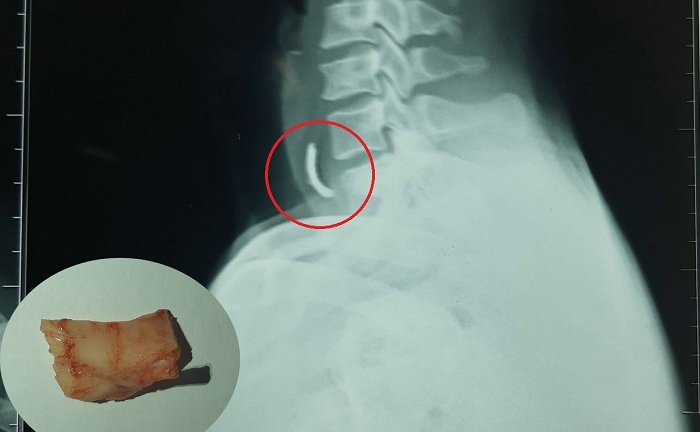

Hóc xương heo khi ăn bún, người đàn ông suýt chết

Người đàn ông ở Đà Nẵng bị mẩu xương heo vướng ngang thực quản sau khi ăn bún, phải vào viện cấp cứu trong tình trạng đau nhức dữ dội, khó thở.